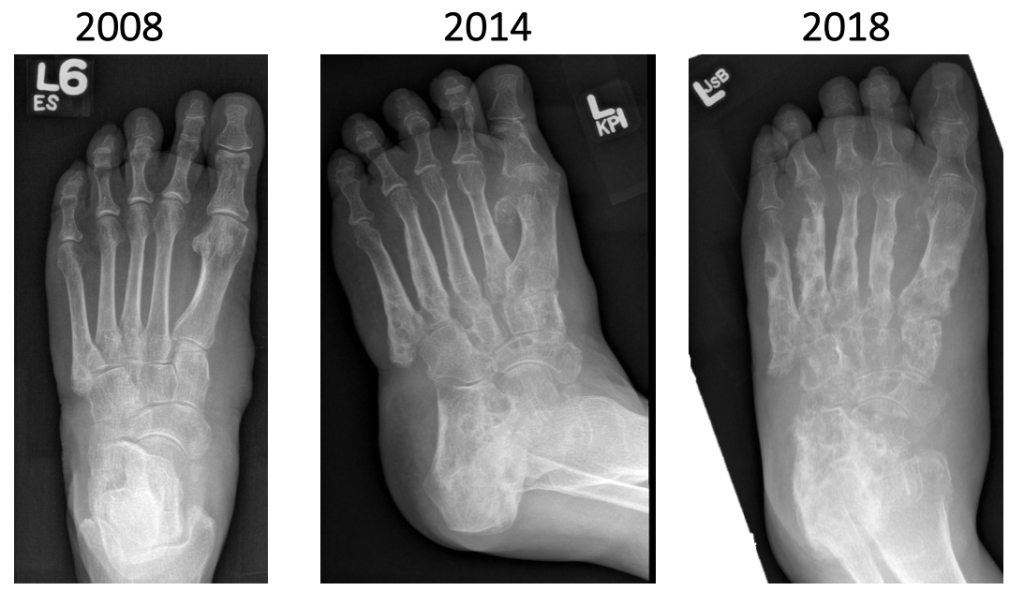

Nhiễm trùng tiến triển chậm trong nhiều tháng hoặc nhiều năm, dần dần lan rộng và phá hủy các cơ, gân, màng và xương liền kề. Không có sự lan truyền toàn thân cũng như không xảy ra các triệu chứng và dấu hiệu gợi ý nhiễm trùng toàn thân. Cuối cùng, tình trạng teo cơ, biến dạng và phá hủy mô sẽ ngăn cản việc sử dụng các chi bị ảnh hưởng.

Việc chẩn đoán u nấm dựa trên biểu hiện lâm sàng và xác định các sinh vật gây bệnh có thể được phát hiện bằng cách kiểm tra trực tiếp các hạt được thải ra từ xoang. Mẫu có thể được lấy bằng phương pháp chọc hút kim nhỏ (FNA) hoặc sinh thiết bằng phẫu thuật. Nhận dạng bằng phản ứng chuỗi Polymerase (PCR) là phương pháp đáng tin cậy nhất nhưng chi phí cao và thiếu kỹ thuật chuẩn hóa. Không có xét nghiệm chẩn đoán nhanh tại điểm chăm sóc nào có thể được sử dụng tại hiện trường. Các kỹ thuật hình ảnh bao gồm tia X, siêu âm, cộng hưởng từ và chụp cắt lớp vi tính có thể được sử dụng để đánh giá mức độ tổn thương và lập kế hoạch quản lý lâm sàng.